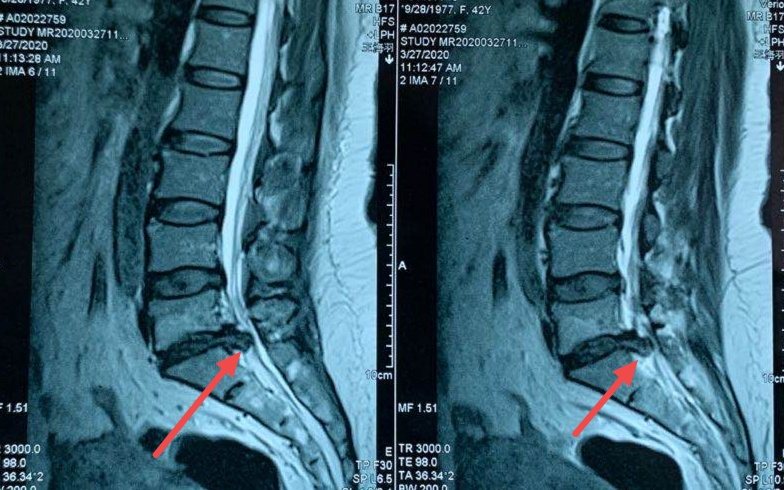

腰5/骶1椎间盘突出位置图

腰椎l3-4膨出,l4-5突出,l5-s1脱出是什么意思?